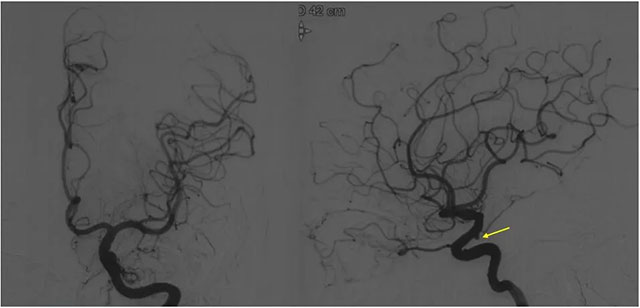

▲ DSA检查显示,左侧窦区动静脉瘘

DSA 检查显示,左侧窦区动静脉瘘,静脉瘘术后改变,供血动脉为枕动脉,通过皮层静脉引流至横窦,左侧椎动脉通过肌支供血汇入枕动脉。